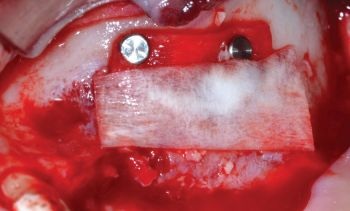

To promote complete reconstruction of the bony wall and prevent the formation of an oroantral communication (which could jeopardize any future procedures in the area), the antrostomy was covered with a double-layered resorbable membrane stabilized with titanium pins (Fig. 14). When it comes to sinus membrane healing, a number of authors demonstrated that mucosal sinus lining is almost completely reformed after two to four weeks

Fig. 14: The antrostomy is protected with a resorbable membrane arranged in a double layer and stabilized with titanium pins